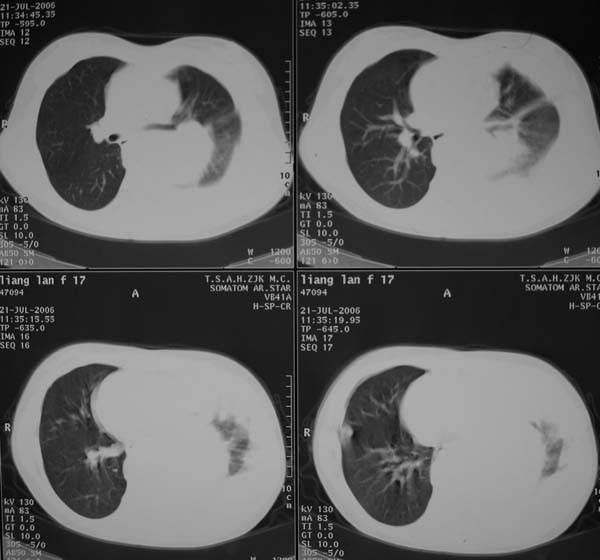

女性,17岁,一年前因股骨病变截肢,现胸憋。

左肺巨大肿块,内散在斑点状高密度骨化影,右肺见多发结节灶,双侧胸膜局限性增厚。有骨肉瘤病史,支持骨肉瘤手术后转移。